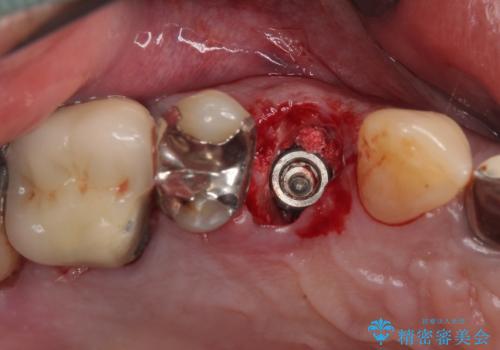

当院での根管治療および歯周外科治療を併用した保存療法、並びに1DAYインプラントによる短期間インプラント治療の双方をご説明し、即日でインプラント治療を選択されました。

仮歯を用意した上で、抜歯即時埋入・即時荷重インプラントによる補綴治療を行うこととしました。

従来のインプラント治療について回った3回の外科手術や半年移動の治療期間とは無縁の、短期間治療を達成することができました。